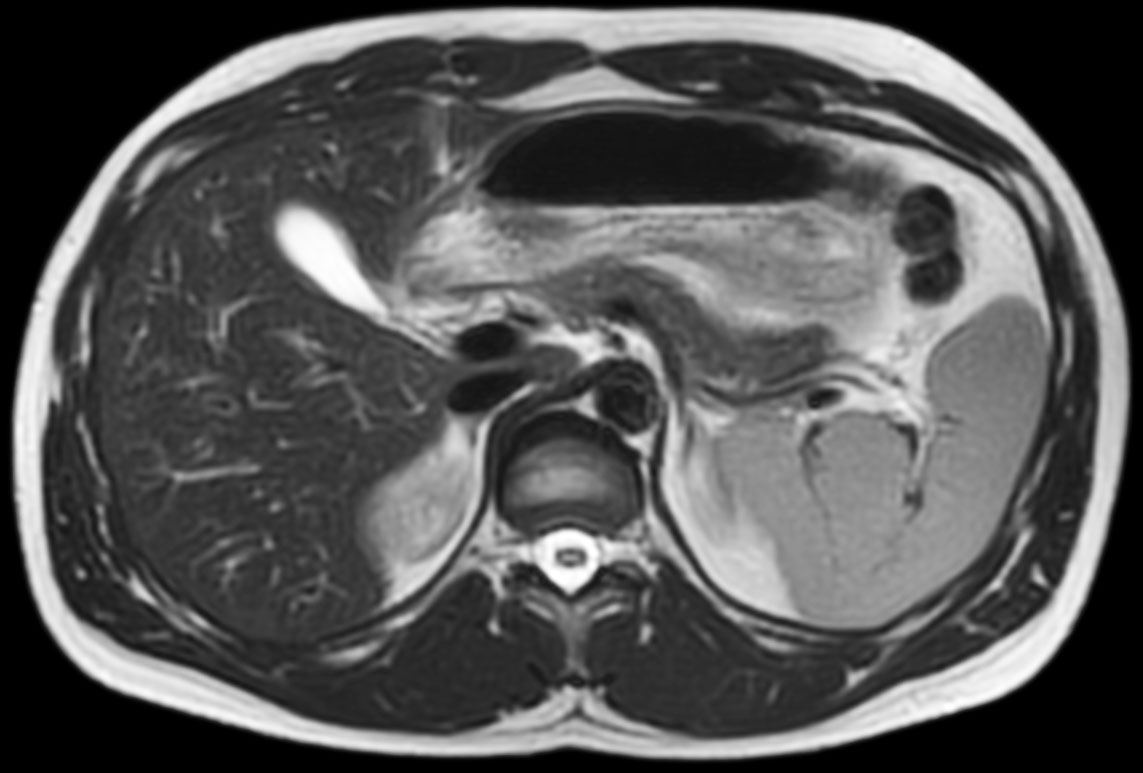

Total torso and liver

• Clinical Application